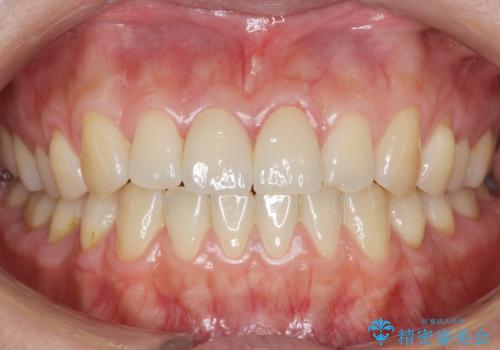

天然歯と見紛うほどの自然な仕上がりに大変喜んで頂けました。

隣在歯を模倣した表面性状・繊細なグラデーション・透明感による再現性の高いセラミッククラウンは、熟練した技工士さんの技術の賜物です。

ジルコニアクラウン エクセレント